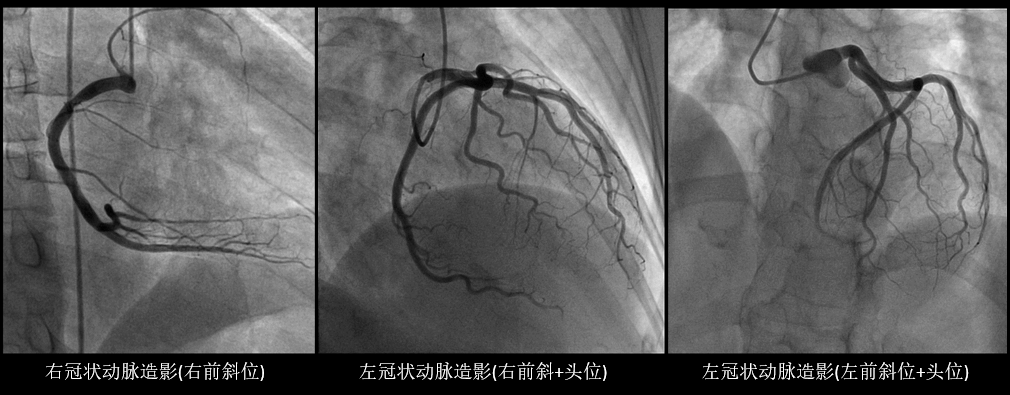

70岁的冯奶奶平素有高血压、冠心病史,近两月来反复出现心前区疼痛,疼痛常持续20分钟以上,并伴有胸闷、气短等症。入院诊断为:冠心病,不稳定心绞痛。为进一步明确诊断,排除病因,避免盲目治疗,经与家属及病人协商签字同意,心脏康复科主任吴志刚为奶奶进行了冠状动脉造影术,手术过程顺利,术中术后奶奶无特殊不适。冠状动脉造影(DSA)提示为左冠优势型,LAD前段开口斑块、中段肌桥,冠脉血流TIMI3级,给后续的治疗指引了正确的方向。

冠脉造影被称为确诊冠心病的“金标准”,它是利用血管造影机来对患者的冠状动脉进行检查,将透明的造影剂快速注入血流,之后血管在X线的照射下显影。在显影下可以评估冠状动脉血管的走向、数量以及畸形等异常表现,可以及时发现冠状动脉内是否存在病变、病变严重程度以及范围。